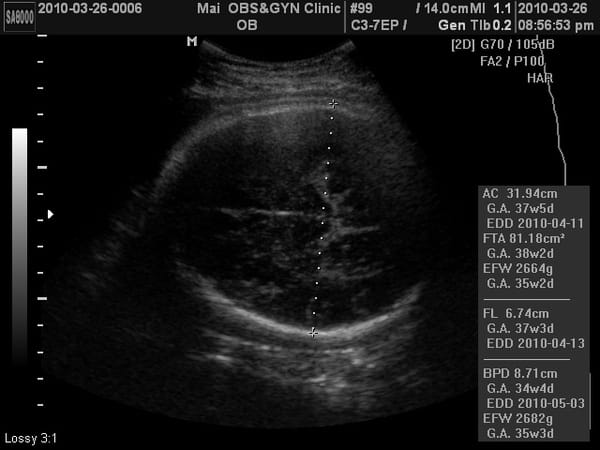

M醫生關心的頭小議題,本周測量頭的大小:8.67cm

如果是8.1cm就有小腦的可能性。

我問醫生那這樣測量不是有落差嗎?

醫生說:頭骨測量是點對點,不像身體是用概括計算的,所以不會有落差,看起來是沒有小腦症的疑慮。